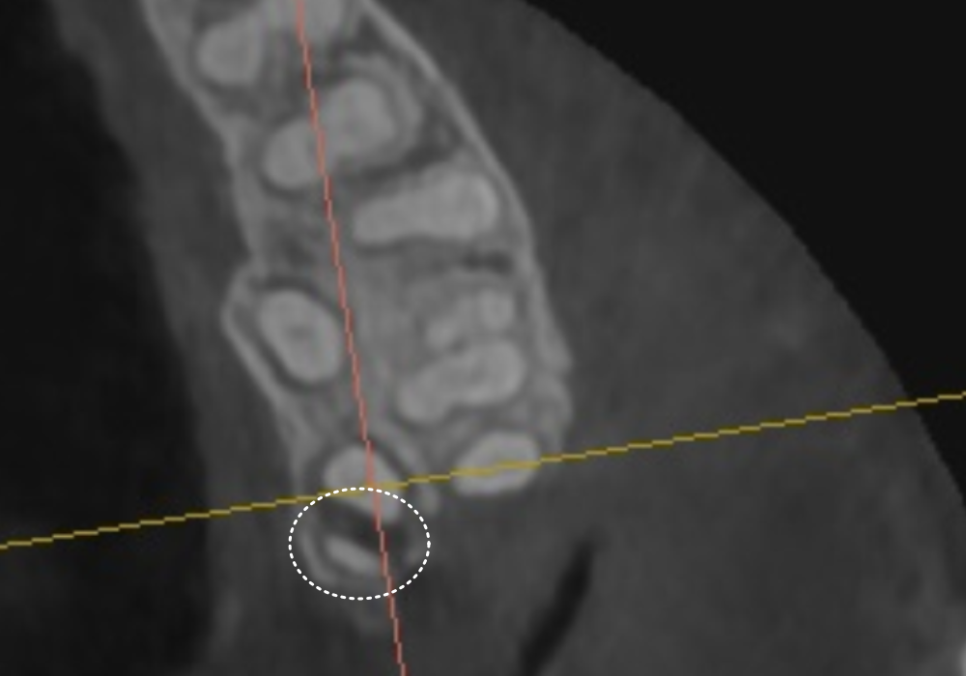

정밀 CT를 통해 분석해 보니,

치아에 금이 가 있는게 보입니다.

250409

맨 끝 어금니(#27)

: 금이 뿌리 쪽으로 깊게 내려간

'수직 치근 파절' 상태였습니다.